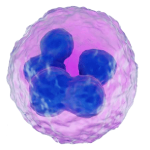

Early Equine Embryology

Embryology - Different Stages of the Early Equine Pregnancy

- Equine embryology - early pregnancy images. A pictorial showing embryonic developmental images...